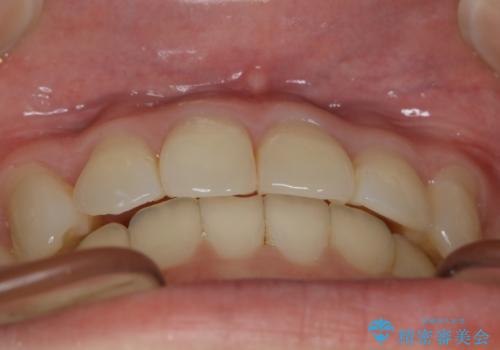

- 笑った時の歯の見え方を治したいとのことで矯正相談にいらっしゃいました。

一見そこまで大きなガタつきはないようにも見えますが、前歯の角度の不揃いや噛み合わせのズレなどから見え方に影響が出てしまっていました。

抜歯は全く必要のないレベルのガタつきだったため、マイクロインプラントを用いて歯全体を後方に移動させていくことできれいな歯並びを獲得することができました。